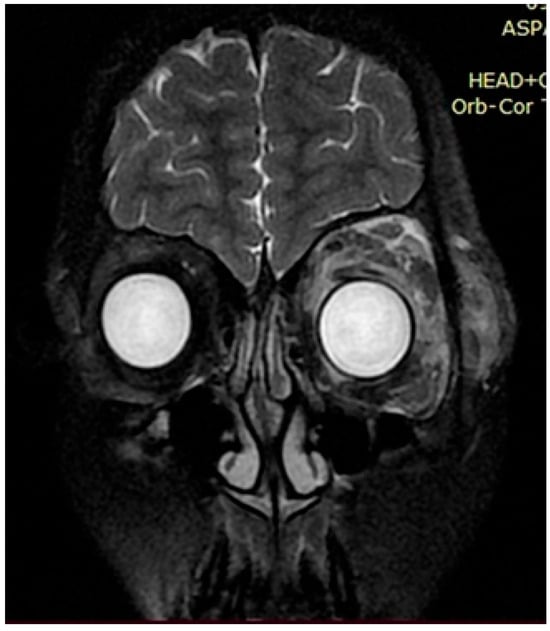

Upon further growth of neural tissues, patients presented with plexiform neurofibromas, located around the eye tract, neck, spinal cord, and groin (examples presented in Figure 3, Figure 4 and Figure 5). A total of 14 patients presented with optic nerve and optic tract glioma as well as retinopathies, retinal angiopathies, declined vision, astigmatism, and other eye pathologies. Many patients complained that eye plexiform neurofibroma occluded their vision, causing gradual vision loss due to lack of accommodation and increased tissue growth.

Figure 3. Case 1, clinical diagnosis of a 14-year-old girl: neurofibromatosis 1, full facial plexiform neurofibroma, especially eye lids, forehead, and the orbits of both eyes, with compression of the eyeballs. With the deletion of the NF1 gene Chr17, deletions NM_000267.4:c.3843delC.